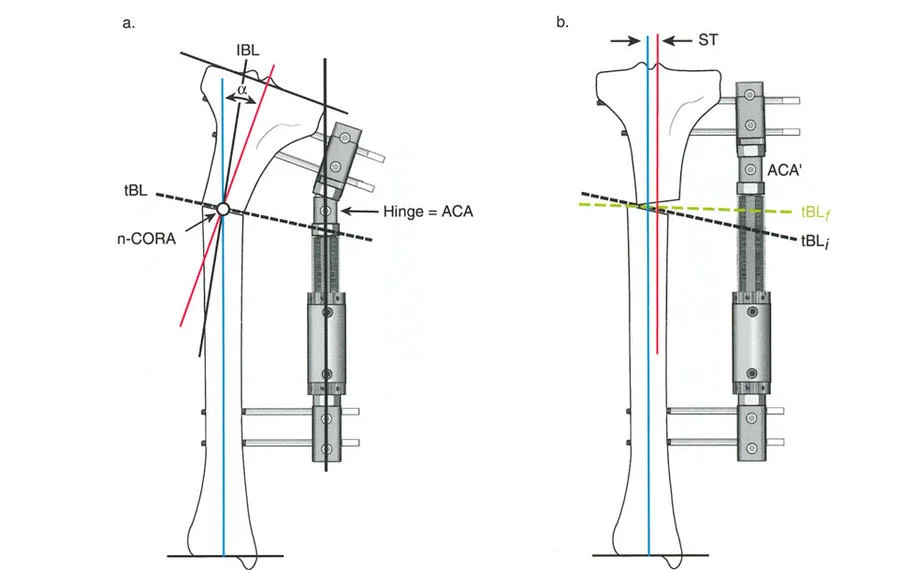

المفصلات القريبة من المفصل وقواعد قطع العظم (Osteotomy Rules)

عند التعامل مع التشوهات الواقعة بالقرب من خط المفصل - مثل التقوس الشديد في الجزء العلوي من الساق (مرض بلونت) أو التشوه الفحجي في الجزء السفلي من عظم الفخذ - يصبح وضع الجهاز مقيدًا هندسيًا. إن المتطلبات البيولوجية للحفاظ على كبسولة المفصل، وتجنب وضع الأسلاك داخل المفصل، ومنع التهاب المفاصل القيحي، غالبًا ما تجبر الجراح على وضع الحلقة المرجعية على مستوى مختلف تمامًا عن مركز دوران الانحراف (CORA) الفعلي.

تحدي مركز دوران الانحراف (CORA) القريب من المفصل

لمطابقة مفصلة المثبت الخارجي مع المستوى الدقيق لمركز دوران الانحراف (CORA)، يجب غالبًا بناء المفصلة فوق أو تحت مستوى الحلقة الفعلية. يُعرف هذا في مبادئ بالي باسم تجميع المفصلة القريبة من المفصل (juxta-articular hinge assembly).

إذا كان مركز دوران الانحراف (CORA) يقع بالقرب من خط المفصل، فإن وضع حلقة إليزاروف القياسية عند هذا المستوى بالضبط مستحيل دون انتهاك مساحة المفصل أو شد الهياكل الكبسولية الحيوية. لذلك، يتم تثبيت الحلقة المرجعية بالعظم الكثيف أو العظم الطويل المتاح، ويتم بناء آلية المفصلة باستخدام قضبان ملولبة، ولوحات توصيل، ودعامات. ثم يتم "إنزالها" (أو رفعها) لتتطابق تمامًا مع مركز دوران الانحراف (CORA) الهندسي الحقيقي.

قواعد بالي لقطع العظم (Osteotomy Rules) في وضع الأجهزة

في المنشآت القريبة من المفصل، غالبًا ما نعتمد على قاعدة قطع العظم 2. نظرًا لأنه لا يمكننا قطع العظم بأمان عند خط المفصل تمامًا (مركز دوران الانحراف CORA)، فإننا نقطع العظم في مستوى أدنى في منطقة الميتافيسيس. بعد تحقيق التصحيح الزاوي عبر المفصلات (محور تصحيح الانحراف ACA)، يتم إعادة محاذاة خطوط المحور الميكانيكي بشكل مثالي، ولكن نهايات العظم في موقع قطع العظم تتحرك بالنسبة لبعضها البعض.

| ACA العمودي | تأكد من أن محور المفصلة (ACA) عمودي تمامًا على مستوى التشوه. | محور ACA مائل سيحدث تشوهًا ثانويًا غير مرغوب فيه (مثل تصحيح التقوس ولكن إحداث الانحناء الأمامي). |